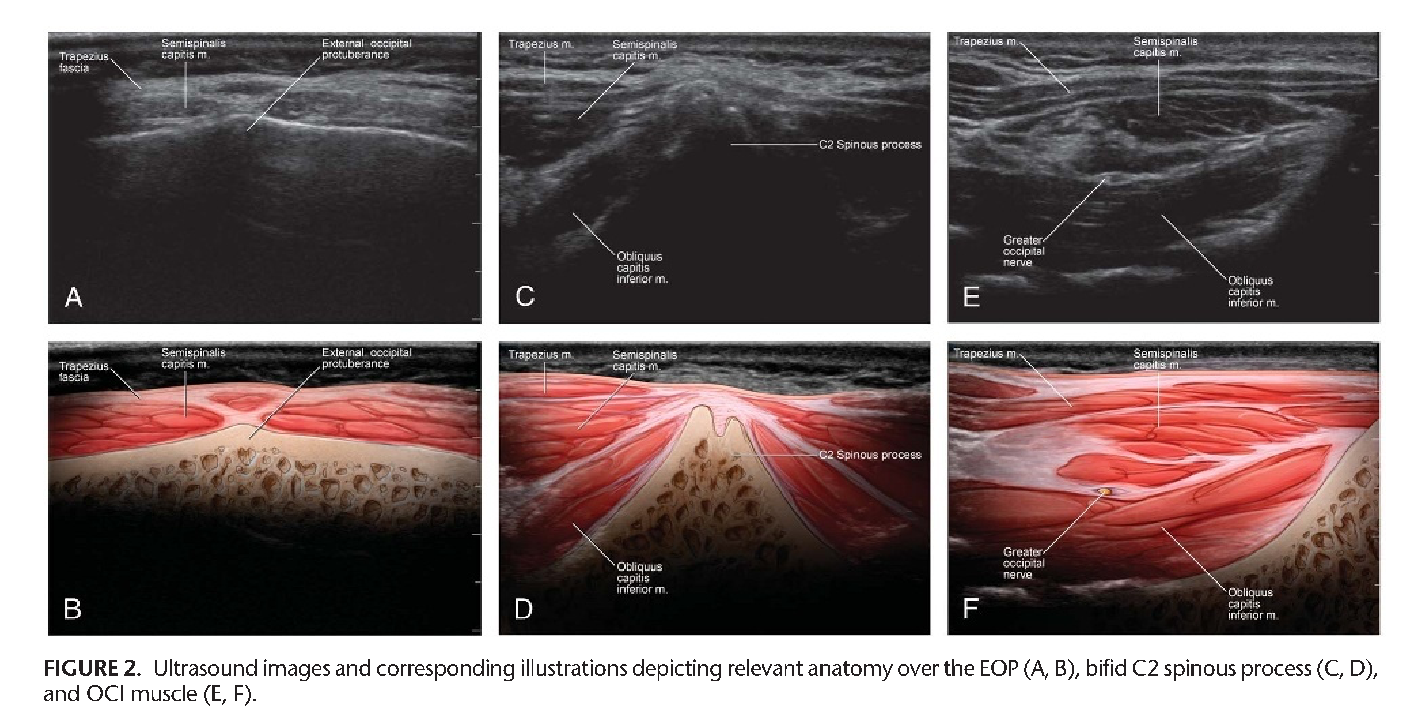

When performing ultrasound-guided occipital nerve blocks, patient positioning is similar to the classic, landmark-based technique where the patient can either be in the prone or sitting position with a flexed neck. Pingree et al described using a standard high-frequency linear transducer. Start by scanning over the occipital protuberance and then move caudally until the bifid C2 spinous process is easily identified. Move the probe laterally until the obliquus capitis inferior muscle is identified. This muscle originates from the C2 spinous process and inserts onto the C1 transverse process (see Figure 2).[5] The probe may need to be rotated in a slight clockwise motion to ensure that it is parallel with the obliquus capitis inferior muscle belly. Proper ultrasound probe positioning will show the semispinalis capitis and trapezius muscle superficial to the GON with the obliquus capitis inferior muscle deep to the GON, as depicted in Figure 2.[5]